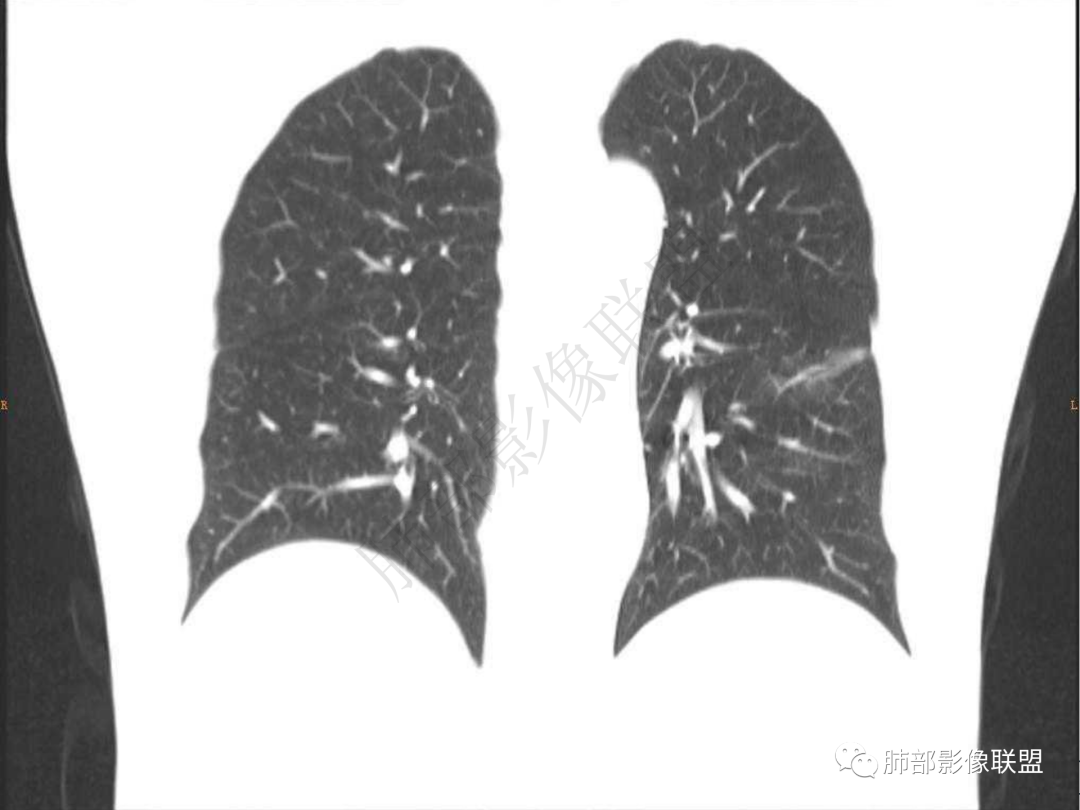

2.左肺下叶团片影,跨背段及内前基底段,实性部分类椭圆形,密度不甚均匀,可见毛刺及棘状突起,未见典型分叶及胸膜凹陷。病灶上下缘可见相应肺段支气管旁进侧出,管壁轻度增厚,未见狭窄阻塞。

3.周边较大范围磨玻璃影,边界相当模糊,小叶增厚明显。注意叶裂另一侧、左肺舌段亦可见磨玻璃影及增厚的小叶间隔。未见明确卫星病灶。

1.病灶不够密实,没有典型分叶,收缩乏力等,支气管未见截断等,缺乏一般肿瘤性肿块特征。

2.周围磨玻璃影边界不清缺乏限制,甚至“激惹”到相邻肺叶,也许提示较明显的炎性水肿。